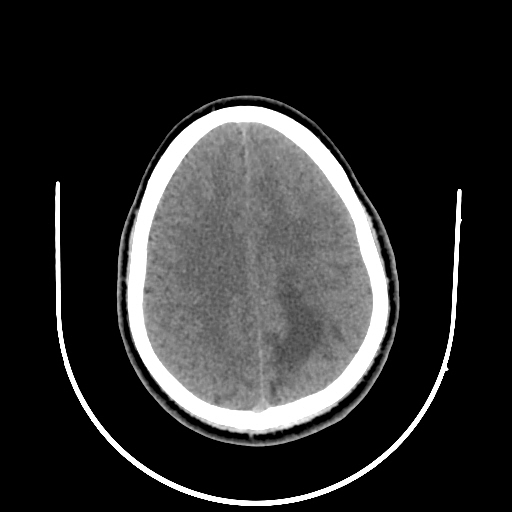

A 35 years old man CT head